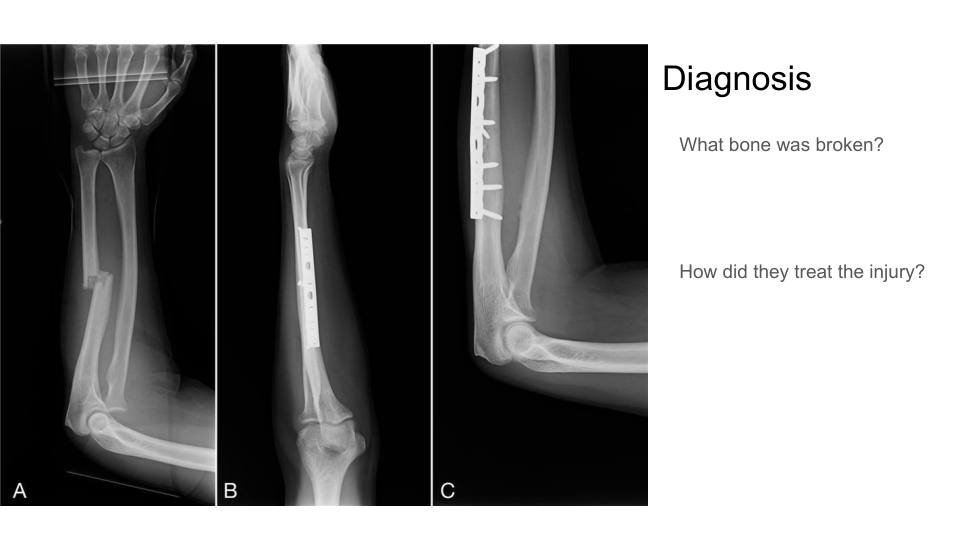

what structure is broken?